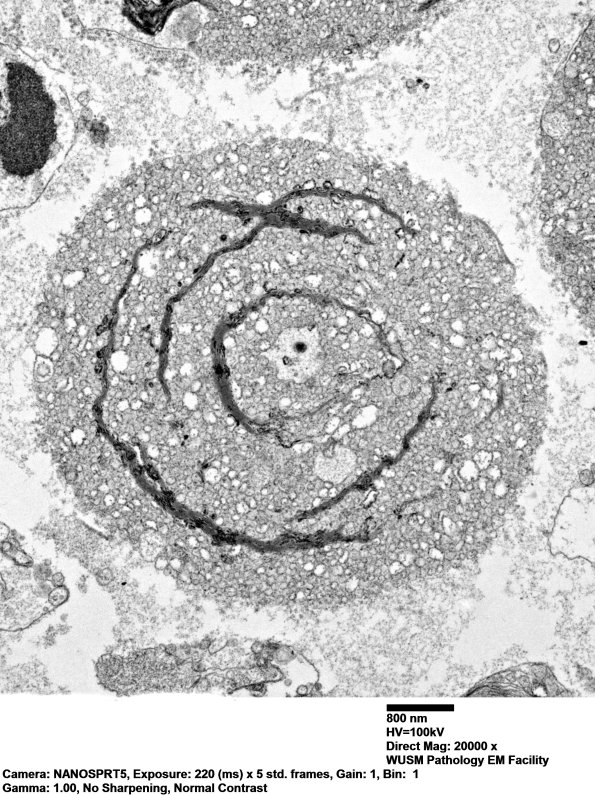

Washington University Experience | PERIPHERAL NEUROPATHY | 0 PNS ARTIFACTS | 19A4 nerve_021 - Copy

Higher magnification image. (electron micrograph)